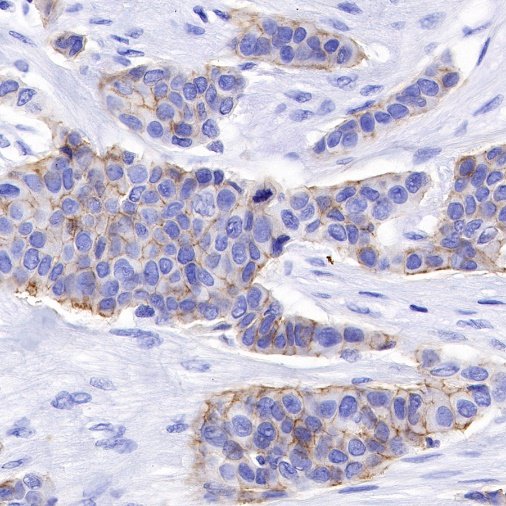

| IHC-P |

1:500 |

Nectin-4 (Nectin cell adhesion molecule 4) is a type I transmembrane cell adhesion molecule belonging to the Nectin family. A homolog formerly known as the poliovirus receptor (PVR/CD155) is also known as the poliovirus receptor associated (PRR) protein. During physiological development, Nectin-4 is specifically expressed during embryonic and fetal development and is very low expressed in adult tissues. It forms physical connections between neighboring cells and is essential for enabling intercellular communication, migration, and other important cellular processes.

Nectin-4 is overexpressed in a variety of tumor cells, and Nectin-4 is used as a marker for cancer recurrence and metastasis, which is associated with poor prognosis of a variety of cancers, including uroepithelial carcinoma, breast cancer, ovarian cancer, pancreatic cancer, non-small cell lung cancer, gastric cancer, hepatocellular carcinoma and bladder cancer. Nectin-4 can promote tumor cell proliferation and differentiation, angiogenesis, lymphangiogenesis and lymphatic metastasis through activation of PI3K/AKT pathway, playing an important role in the occurrence and metastasis of cancer. Nectin-4 is also an independent biomarker associated with poor overall survival in some cancer types. Due to its high specific expression in tumors, drug studies targeting this target have emerged.